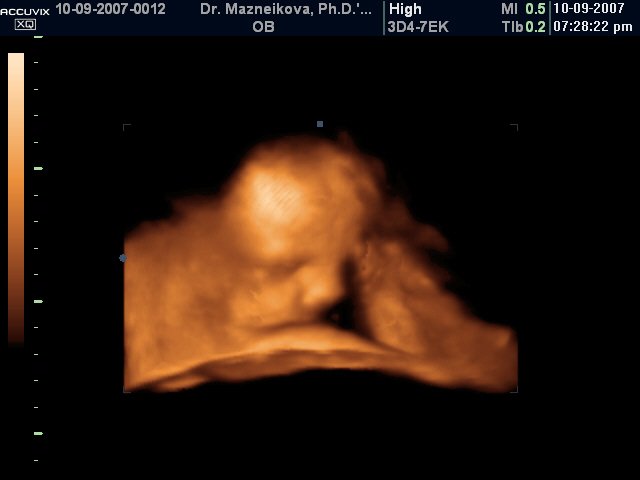

, крачетата и те едни дълги и също избързват с една-две седмици (ама забравих колко бяха) и накрая изненадата - тегло 3318 гр.

Само проблем е, че тя добре си е наместила главичката обаче е малко лицево към родовия канал, а трябвало тилно и ако остане така и секцио може да се наложи.